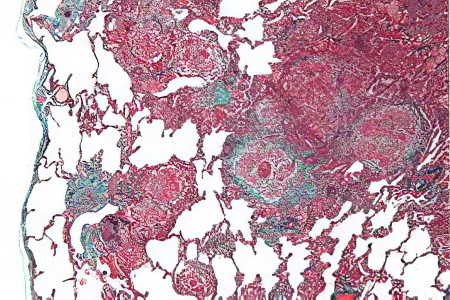

Гистологическая картина ЭАА

В большинстве случаев у пациентов с экзогенным аллергическим альвеолитом наблюдаются гранулёмы без творожистого налёта. Эти изменения фиксируются у 79-90% больных.

Чтобы не путать гранулёмы при экзогенном аллергическом альвеолите и саркоидозе, следует обратить внимание на несколько ключевых отличий:

- Гранулёмы при экзогенном аллергическом альвеолите меньше по размеру.

- У них отсутствуют четкие границы.

- В составе гранулём больше лимфоцитов.

- Альвеолярные стенки утолщены и имеют лимфоцитарные инфильтраты.

После устранения контакта с антигеном гранулёмы могут исчезнуть самостоятельно в течение полугода.

Воспалительный процесс при экзогенном аллергическом альвеолите обусловлен лимфоцитами, моноцитами, макрофагами и плазматическими клетками. Пенистые альвеолярные макрофаги накапливаются внутри альвеол, в то время как лимфоциты располагаются в интерстиции. На начальных стадиях заболевания у пациентов можно обнаружить белковый и фибринозный выпот внутри альвеол. Также у больных выявляется бронхиолит, лимфатические фолликулы и перибронхиальные воспалительные инфильтраты в малых дыхательных путях.

Таким образом, для этого заболевания характерна триада морфологических изменений:

- Альвеолит.

- Гранулёматоз.

- Бронхиолит.

Хотя иногда один из этих признаков может отсутствовать. Редко у пациентов с экзогенным аллергическим альвеолитом развивается васкулит, который диагностируется посмертно, что фиксируется в соответствующих документах. При лёгочной гипертензии у больных наблюдается гипертрофия артерий и артериол.

Хроническое течение экзогенного аллергического альвеолита приводит к фибринозным изменениям, которые могут варьироваться по интенсивности. Однако такие изменения не являются уникальными для экзогенного аллергического альвеолита и встречаются также при других хронических заболеваниях лёгких. Поэтому их нельзя считать патогномичным признаком. При длительно текущем альвеолите у пациентов лёгочная паренхима претерпевает патологические изменения, напоминающие сотовое лёгкое.